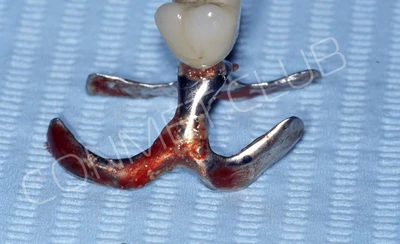

Для примера приводим одну из первых, фантомных работ. Этот имплантат никому не устанавливался и даже печатался на 3D принтере не из титана, а из стали, но подобные работы позволили выявить несколько скрытых проблем и избежать их при реальном, клиническом применении.

Имплантат напечатали из особого, биосовместимого, медицинского титана на предприятии имеющим соответствующую медицинскую лицензию. Толщина имплантата составила 0,8 мм, а вес всего несколько грамм!